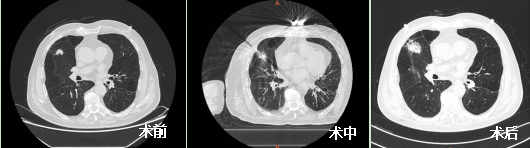

近日,我院呼吸介入團隊為一例葉間裂旁肺結節患者進行了微波消融治療,術中消融針精準命中靶病灶,術后暈征較好地覆蓋病灶,恢復良好,術后三天患者好轉辦理出院。

為進一步進行治療,王開金副主任帶領胡學進副主任醫師、陳進主治醫師等呼吸介入團隊聯合麻醉科王艷冰副主任進行了縝密的術前討論,綜合評估患者的整體狀況,術前討論決定為患者右肺上葉高危結節進行微波消融術。做好充分術前準備后,團隊于6月16日CT引導下行右肺上葉結節微波消融術,術程順利,全程無痛,術后無并發癥出現。現患者愈后良好,于術后第三天辦理出院,并擬1月后對右肺中葉結節行氬氦刀冷凍消融術。

劉爺爺符合專家共識推薦的第一、四條,但他的肺結節緊鄰葉間裂,極易出現氣胸及支氣管胸膜瘺,經過我院呼吸介入團隊認真的術前準備、精準的術中布針,較好地完成了手術。此次微波消融術的成功開展,標志著呼吸與危重癥醫學科微創治療技術再上新臺階。為患者身心健康和生命安全保駕護航,重慶醫科大學附屬璧山醫院呼吸與危重癥醫學科一直在努力!